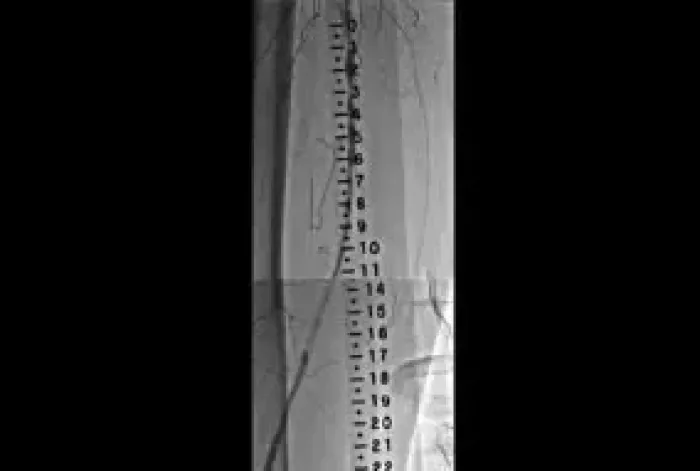

TREATING SFA IN-STENT RESTENOSIS: CARL’S STORY

How the VIABAHN® Device improved Carl’s mobility and quality of life.